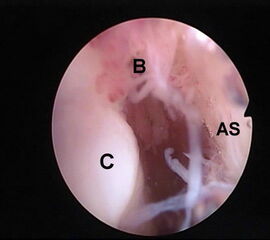

Abbildung 5-7, Video 2

Zunächst wird die Bursektomie (Abb. 5: gerötete Bursa subachillea; C=Calcaneus, B=Bursa, AS=Achillessehne) mit der Radiofrequenzsonde durchgeführt und die Haglundexostose dargestellt. Alternativ kann die Bursektomie mit einem Shaver durchgeführt werden. Hierbei sollte der Ansatz der Achillessehne kaudal einsehbar sein (Abb. 6: C=Calcaneus, AS=Achillessehne) und unbedingt die gesamte mediolaterale Ausdehnung der posterioren Calcaneusfläche erfasst werden (Abb. 7). Häufig liegen Anteile der Exostose weit medial und/oder lateral und werden übersehen.